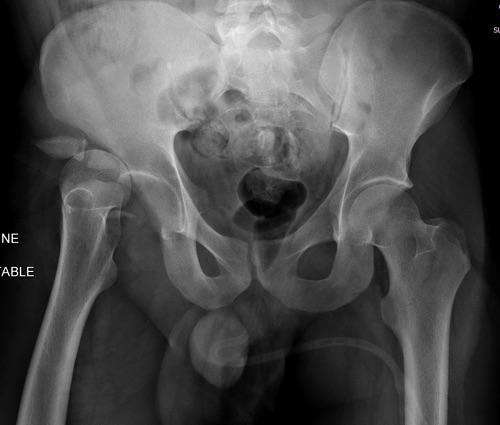

Данная картина показывает очень редкий перелом передней колонны, но

перед операцией еще раз надо просмотреть обещанные дополнительные КТ срезы.

Фиксация переломов передней колонны намного легче, чем остальных

переломов вертлужной впадины. Любой доступ: Smith Petersen, Stoppa или

ilio-inguinal. Как фиксировать перелом зависит от желания врача, можно

пустить пластину по pelvic brim (linea terminalis) или более щадящее из

верхнего окна пластиной, а переднюю колонну длинными межколонными винтами.